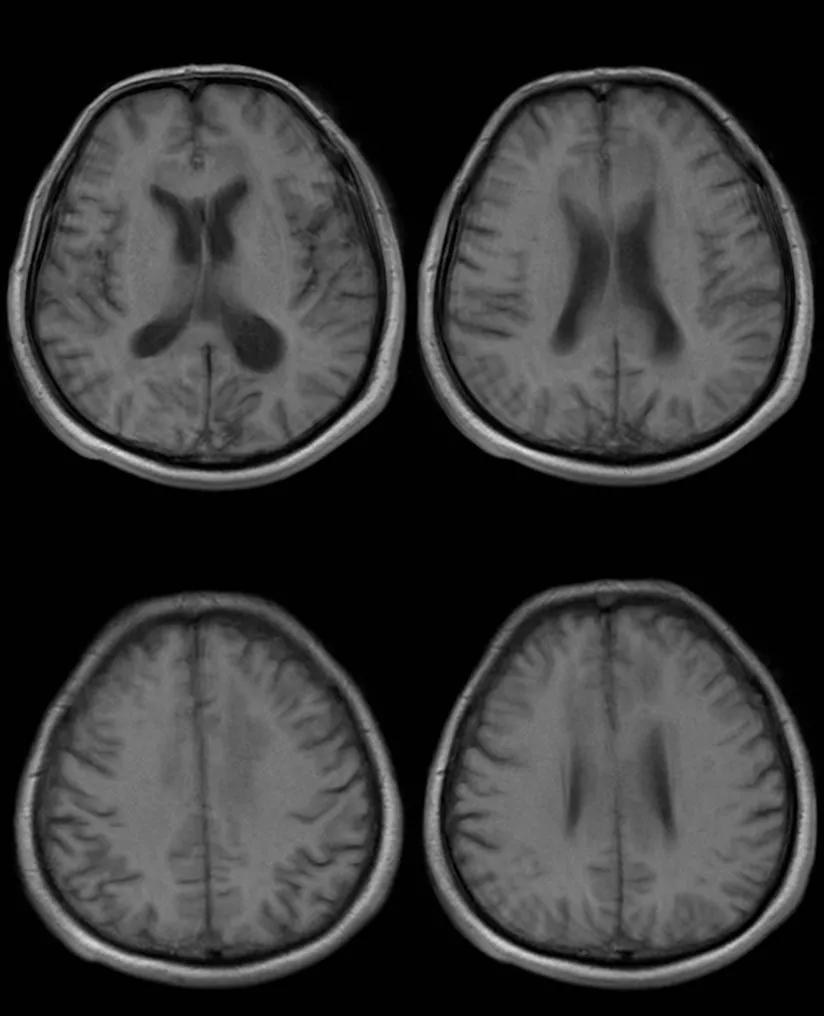

- 急性期表现为胼胝体弥漫性肿胀,T1WI呈稍低信号,T2WI及FLAIR呈稍高信号,以矢状位观察最佳,可单独累及胼胝体压部或整个胼胝体,DWI呈高信号,ADC图呈低信号,部分患者可观察到脑室周围白质或内囊受累,少见皮层受累,表现为扩散受限,不强化和强化病例均可见到。如果增强扫描可见胼胝体有不同程度强化,呈小灶状或不规则斑片状,系血脑屏障破坏所致(如本例),本例患者处于急性期。

31岁,男性,长期饮酒,出现急性失语、短期注意力和记忆力缺陷,胼胝体及半卵圆中心对称性异常信号,扩散受限,未见强化,经过维生素B1/6/9/12治疗后病灶吸收明显,诊断为原发性胼胝体变性急性期。